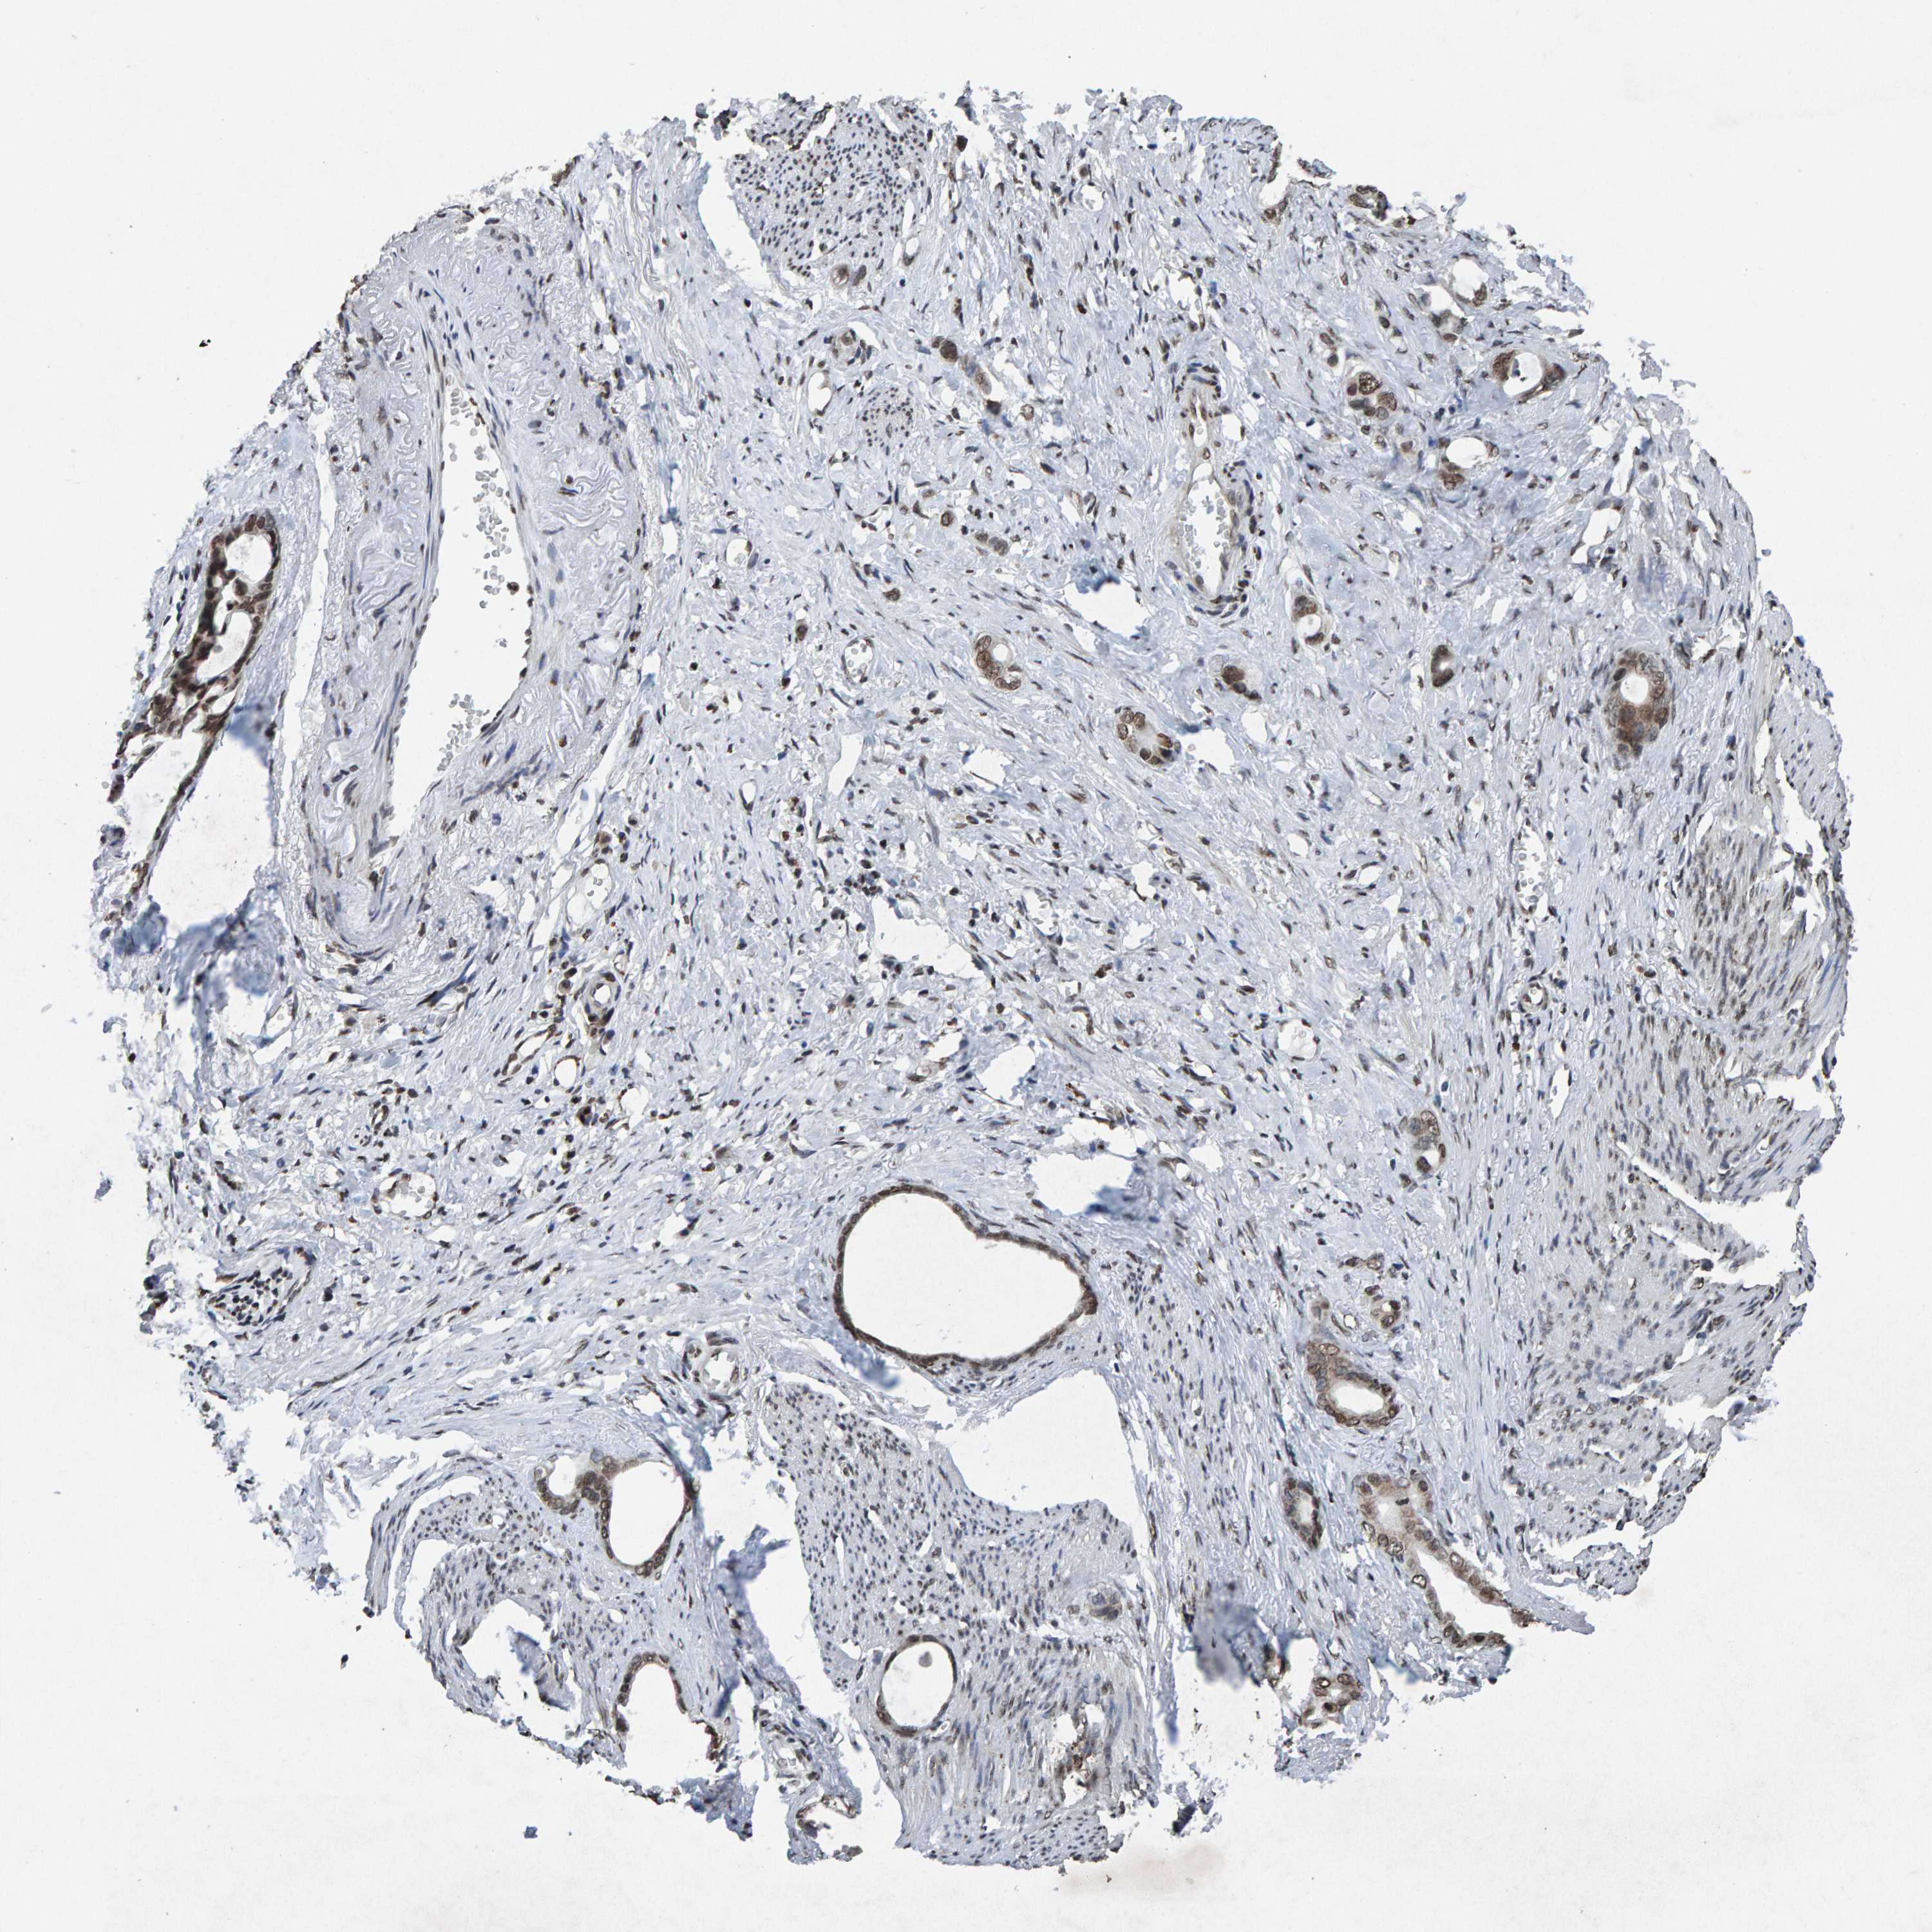

STOMACH CANCER - Protein expressioni

A mouse-over function shows sample information and annotation data. Click on an image to view it in a full screen mode. Samples can be filtered based on level of antibody staining by selecting one or several of the following categories: high, medium, low and not detected. The assay and annotation is described here.

Note that samples used for immunohistochemistry by the Human Protein Atlas do not correspond to samples in the TCGA dataset.

Antibody stainingi

Antibody staining in the annotated cell types in the current human tissue is reported as not detected, low, medium, or high, based on conventional immunohistochemistry profiling in selected tissues. This score is based on the combination of the staining intensity and fraction of stained cells.

Each image is clickable and will lead to virtual microscopy that enables deeper exploration of all samples and also displays staining intensity scores, fraction scores and subcellular localization as well as patient and tissue information for each sample.

Antibody HPA057236

Antibody CAB022549

Staining

High

Medium

Low

Not detected

Intensity

Strong

Moderate

Weak

Negative

Quantity

>75%

75%-25%

<25%

None

Location

Nuclear

Cytoplasmic/membranous

Cytoplasmic/membranous,nuclear

Adenocarcinoma, NOS

Adenocarcinoma, High grade